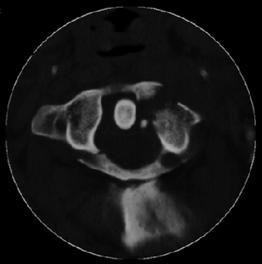

TRAUMA CERVICALA

Fractura

Jefferson

Fractura Jefferson Fragmente

osoase la stanga apofizei odontoide

Fractura Jefferson  Fractura spanzuratului

Aspect CT